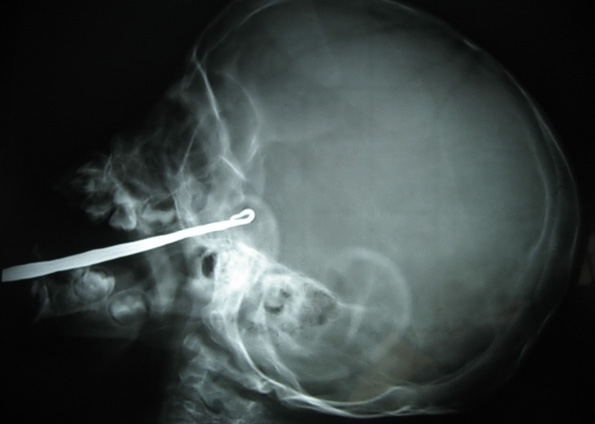

Imagem de raio X mostra alicate cravado no rosto do garoto Xiao Hu, na cidade chinesa de Changsha. O menino de 2 anos caiu acidentalmente sobre a ferramenta, que entrou pela parte superior de sua boca e atingiu seu cérebro. Xiao Huo, que mora na cidade de Yongshun, na província de Hunan, passou por uma cirurgia na segunda-feira (25) e está se recuperando. Bombeiros cortaram a maior parte do metal, deixando cerca de 10 cm saindo de seu rosto. O objets entrou cerca de 5cm dentro do cérebro do caroto.